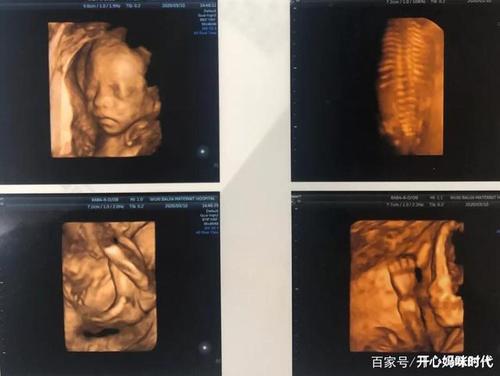

怀孕四维彩超图片,怀孕6周彩超图片

孕期四维_四维彩超_孕期_四维彩超照_母婴_孕产经验

四维彩超_胎儿_孕期_母婴_孕产经验

22周四维彩超顺利通过!感恩!

怀孕日记##四维彩超

孕期四维彩超主要检查什么?胎儿这些"小秘密",你都发现了吗?

四维彩超清晰图片

四维彩超图片

四维彩超图片真实